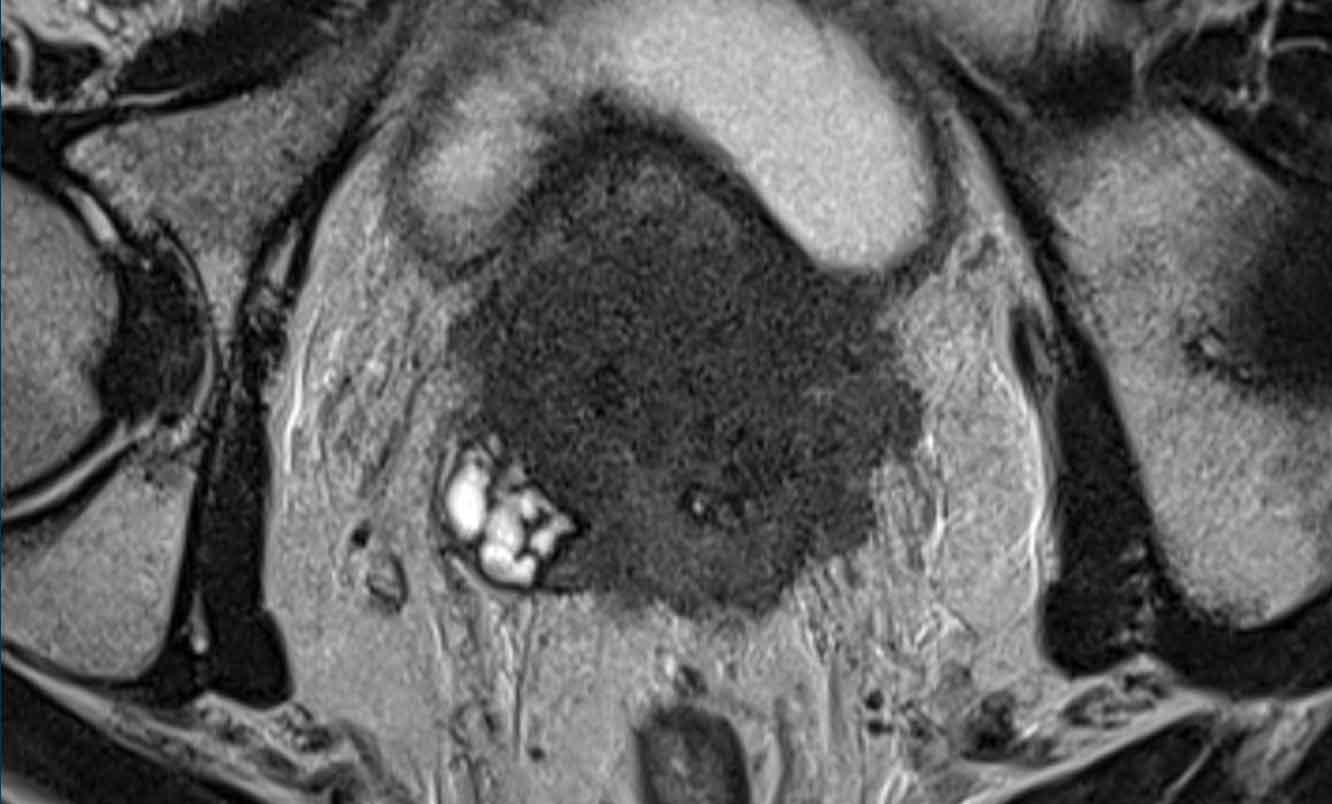

Hãy quan sát hình ảnh trước và mô tả những gì bạn thấy.

Một tổn thương kích thước 16 mm (không hiển thị phép đo) được phát hiện, nằm ở phía sau vùng ngoại vi của phần giữa tuyến tiền liệt bên phải.

Tổn thương này được xếp vào phân loại PI-RADS 5, dựa trên giảm tín hiệu rõ rệt trên ADC và tăng tín hiệu rõ rệt trên DWI (điểm 5 – chuỗi xung chính), đối chiếu với giảm tín hiệu rõ rệt trên chuỗi xung T2W (điểm 5).

Điểm Gleason là 3+4, cho thấy nguy cơ trung bình của một ung thư có tính xâm lấn cao.

Tổn thương không tiếp xúc với vỏ bao giả và không có dấu hiệu xâm lấn ra ngoài tuyến tiền liệt.